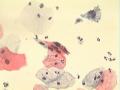

女性、55岁,接触性出血

HSIL

HSIL。

好像是干封片,建议采用湿封片。